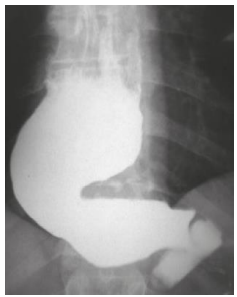

Mulher, 56 anos, portadora de megaesôfago grau IV (imagem abaixo). Admitida na enfermaria com desnutrição

grave. Após instalação de sonda nasoenteral e dieta, passou a apresentar exames laboratoriais compatíveis com

síndrome de realimentação.